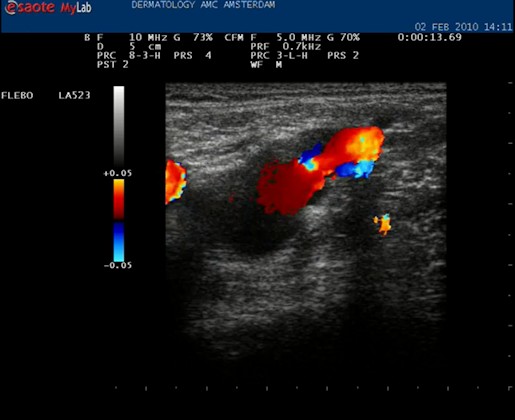

| Knijp in het been onder de echo kop. Het bloed stroomt omhoog en dat geeft een blauwe kleur (normaal) maar bij het loslaten stroomt het bloed terug en wordt het gehele vat langdurig rood. Nu weten we dat de kleppen in deze vene kapot zijn. De kleuren blauw (omhoog stromend, veneus) en rood (omlaag stromend) worden alleen goed weergegeven als de echokop goed wordt gehouden, met het pijltje omhoog. |

| Knijpen in het been: het vat wordt geheel rood bij loslaten: de vena saphena magna is insufficiënt. |

| Met de duplex kan ook de reflux over het vat worden gemeten. |